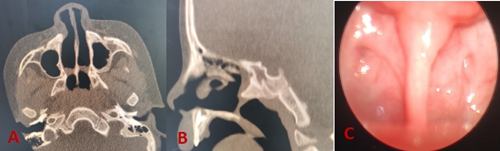

圖A、圖B:鼻竇CT水平位、矢狀位均提示雙側(cè)后鼻孔膜性閉鎖圖C:70°鼻內(nèi)鏡下經(jīng)鼻咽部見雙側(cè)后鼻孔閉鎖

后鼻孔閉鎖為兒童少見的先天性鼻部畸形,是以鼻腔和鼻咽之間完全堵塞為特征的一種罕見顱面缺損。后鼻孔閉鎖不僅會(huì)導(dǎo)致寶寶出現(xiàn)頻繁的鼻塞流涕、呼吸困難,影響鼻腔正常通氣及引流,嚴(yán)重還可能造成鼻面部及智力的發(fā)育,甚至窒息死亡。